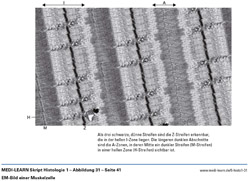

• EM-Bild einer Muskelzelle